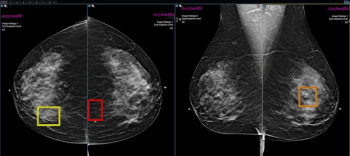

New research suggests that AI-powered assessment of digital breast tomosynthesis (DBT) for short-term breast cancer risk may help address racial disparities with detection and shortcomings of traditional mammography in women with dense breasts.

Emerging research from the RSNA conference suggests that two-dimensional mammography would only detect 41 percent of detectable breast cancer.

In a recent interview, Sarah Friedewald, MD, discussed new study findings for an adjunctive AI software for digital breast tomosynthesis (DBT) that revealed nearly equivalent sensitivity and specificity rates for breast cancer across a diverse cohort.

In a multicenter study involving over 747,000 women who had mammography screening, those who paid for AI-enhanced screening had a 21 percent higher recall rate and a 15 percent higher positive predictive value (PPV) for breast cancer, according to research presented at the Radiological Society of North America (RSNA) conference.